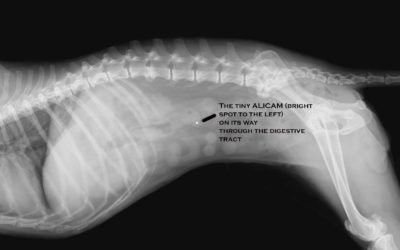

Take One Camera and Call Me In The Morning

Swallowable camera photographs entire length of dog’s digestive track for 360 degree, painless, diagnosis of canine digestive disorders.